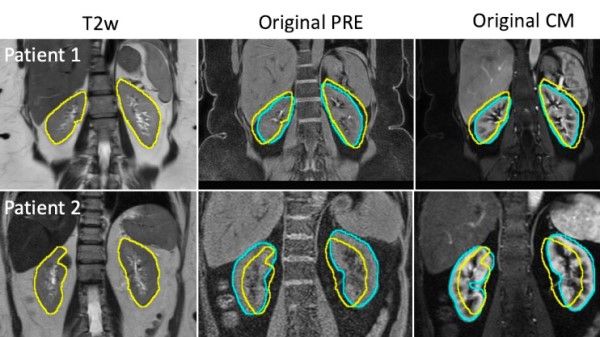

RANO misses to capture tumor growth especially non-enhancing portions of the (HGG) GBMs-in Post con sequences and tumor volumetrics sure is the future to these tumor growth analyses and quantification of treatment response/s.